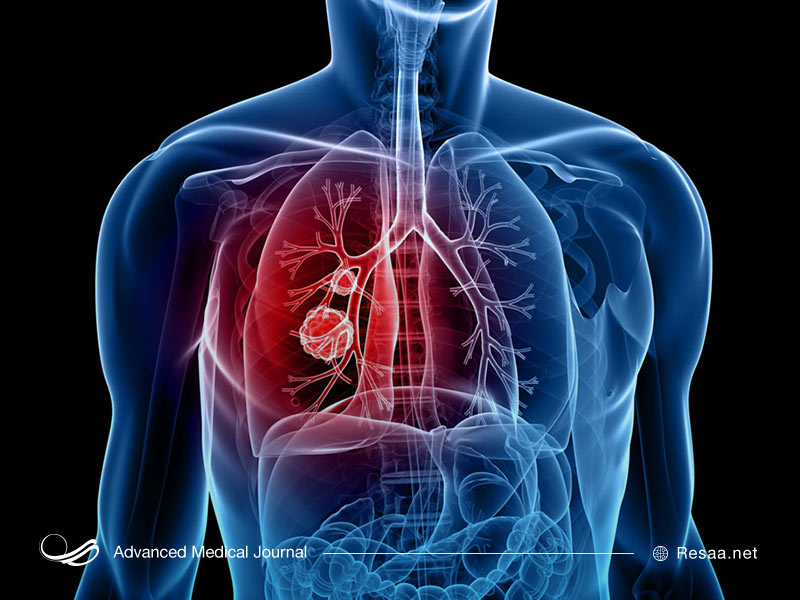

مانند سایر سرطانها، سرطان ریه هنگامی رخ میدهد که فرآیندهای طبیعی تقسیم و رشد سلولی مختل میشود و این باعث توسعه غیرقابل کنترل سلولهای غیرطبیعی میشود. در فرآیند بیماری، سلولها به یک توده یا تومور تبدیل میشوند. هر رشد غیرطبیعی در بدن که مستقیماً به بافتها و اندامها حمله کرده و به قسمتهای دیگر بدن نیز سرایت میکند و حتی با برداشتن تومورها، غدههای جدید رشد میکنند، «سرطان ریه بدخیم» خوانده میشود.

بیشتر سرطانهای ریه در پوشش برونشها (معابر هوایی که از قسمت نای یا لوله تنفسی جدا میشوند) رشد میکنند. سرطان ریه همچنین میتواند در غدد زیرآستر برونشها، غالباً در نواحی بیرون ریهها ایجاد شود. به طور کلی، سرطانهای ریه به دو نوع اصلی بعنی سلول کوچک و سلول غیرکوچک تقسیم میشوند. هر یک از دو سرطان ریه به شیوههای مختلفی رشد میکنند:

علائم پیشرفته سرطان ریه شامل سرفه، تنگی نفس، درد در قفسه سینه، خستگی و یا کاهش وزن به صورت غیرعمدی است. علائم و نشانههایی که ممکن است در صورت گسترش سرطان به نقاط دیگر ظاهر شوند شامل درد استخوان، سردرد، ضعف عضلات و افتادگی پلک است.